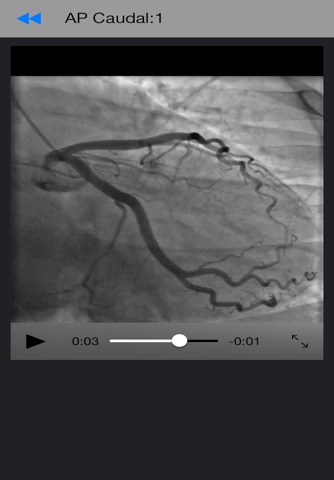

CathLab App provides easy to access information for education in the setting of cardiac catheterization laboratory. The information elements include description of different procedural basics as well as illustrations. In addition video clips inside the app and from world wide web supplement the content in a meaningful way.